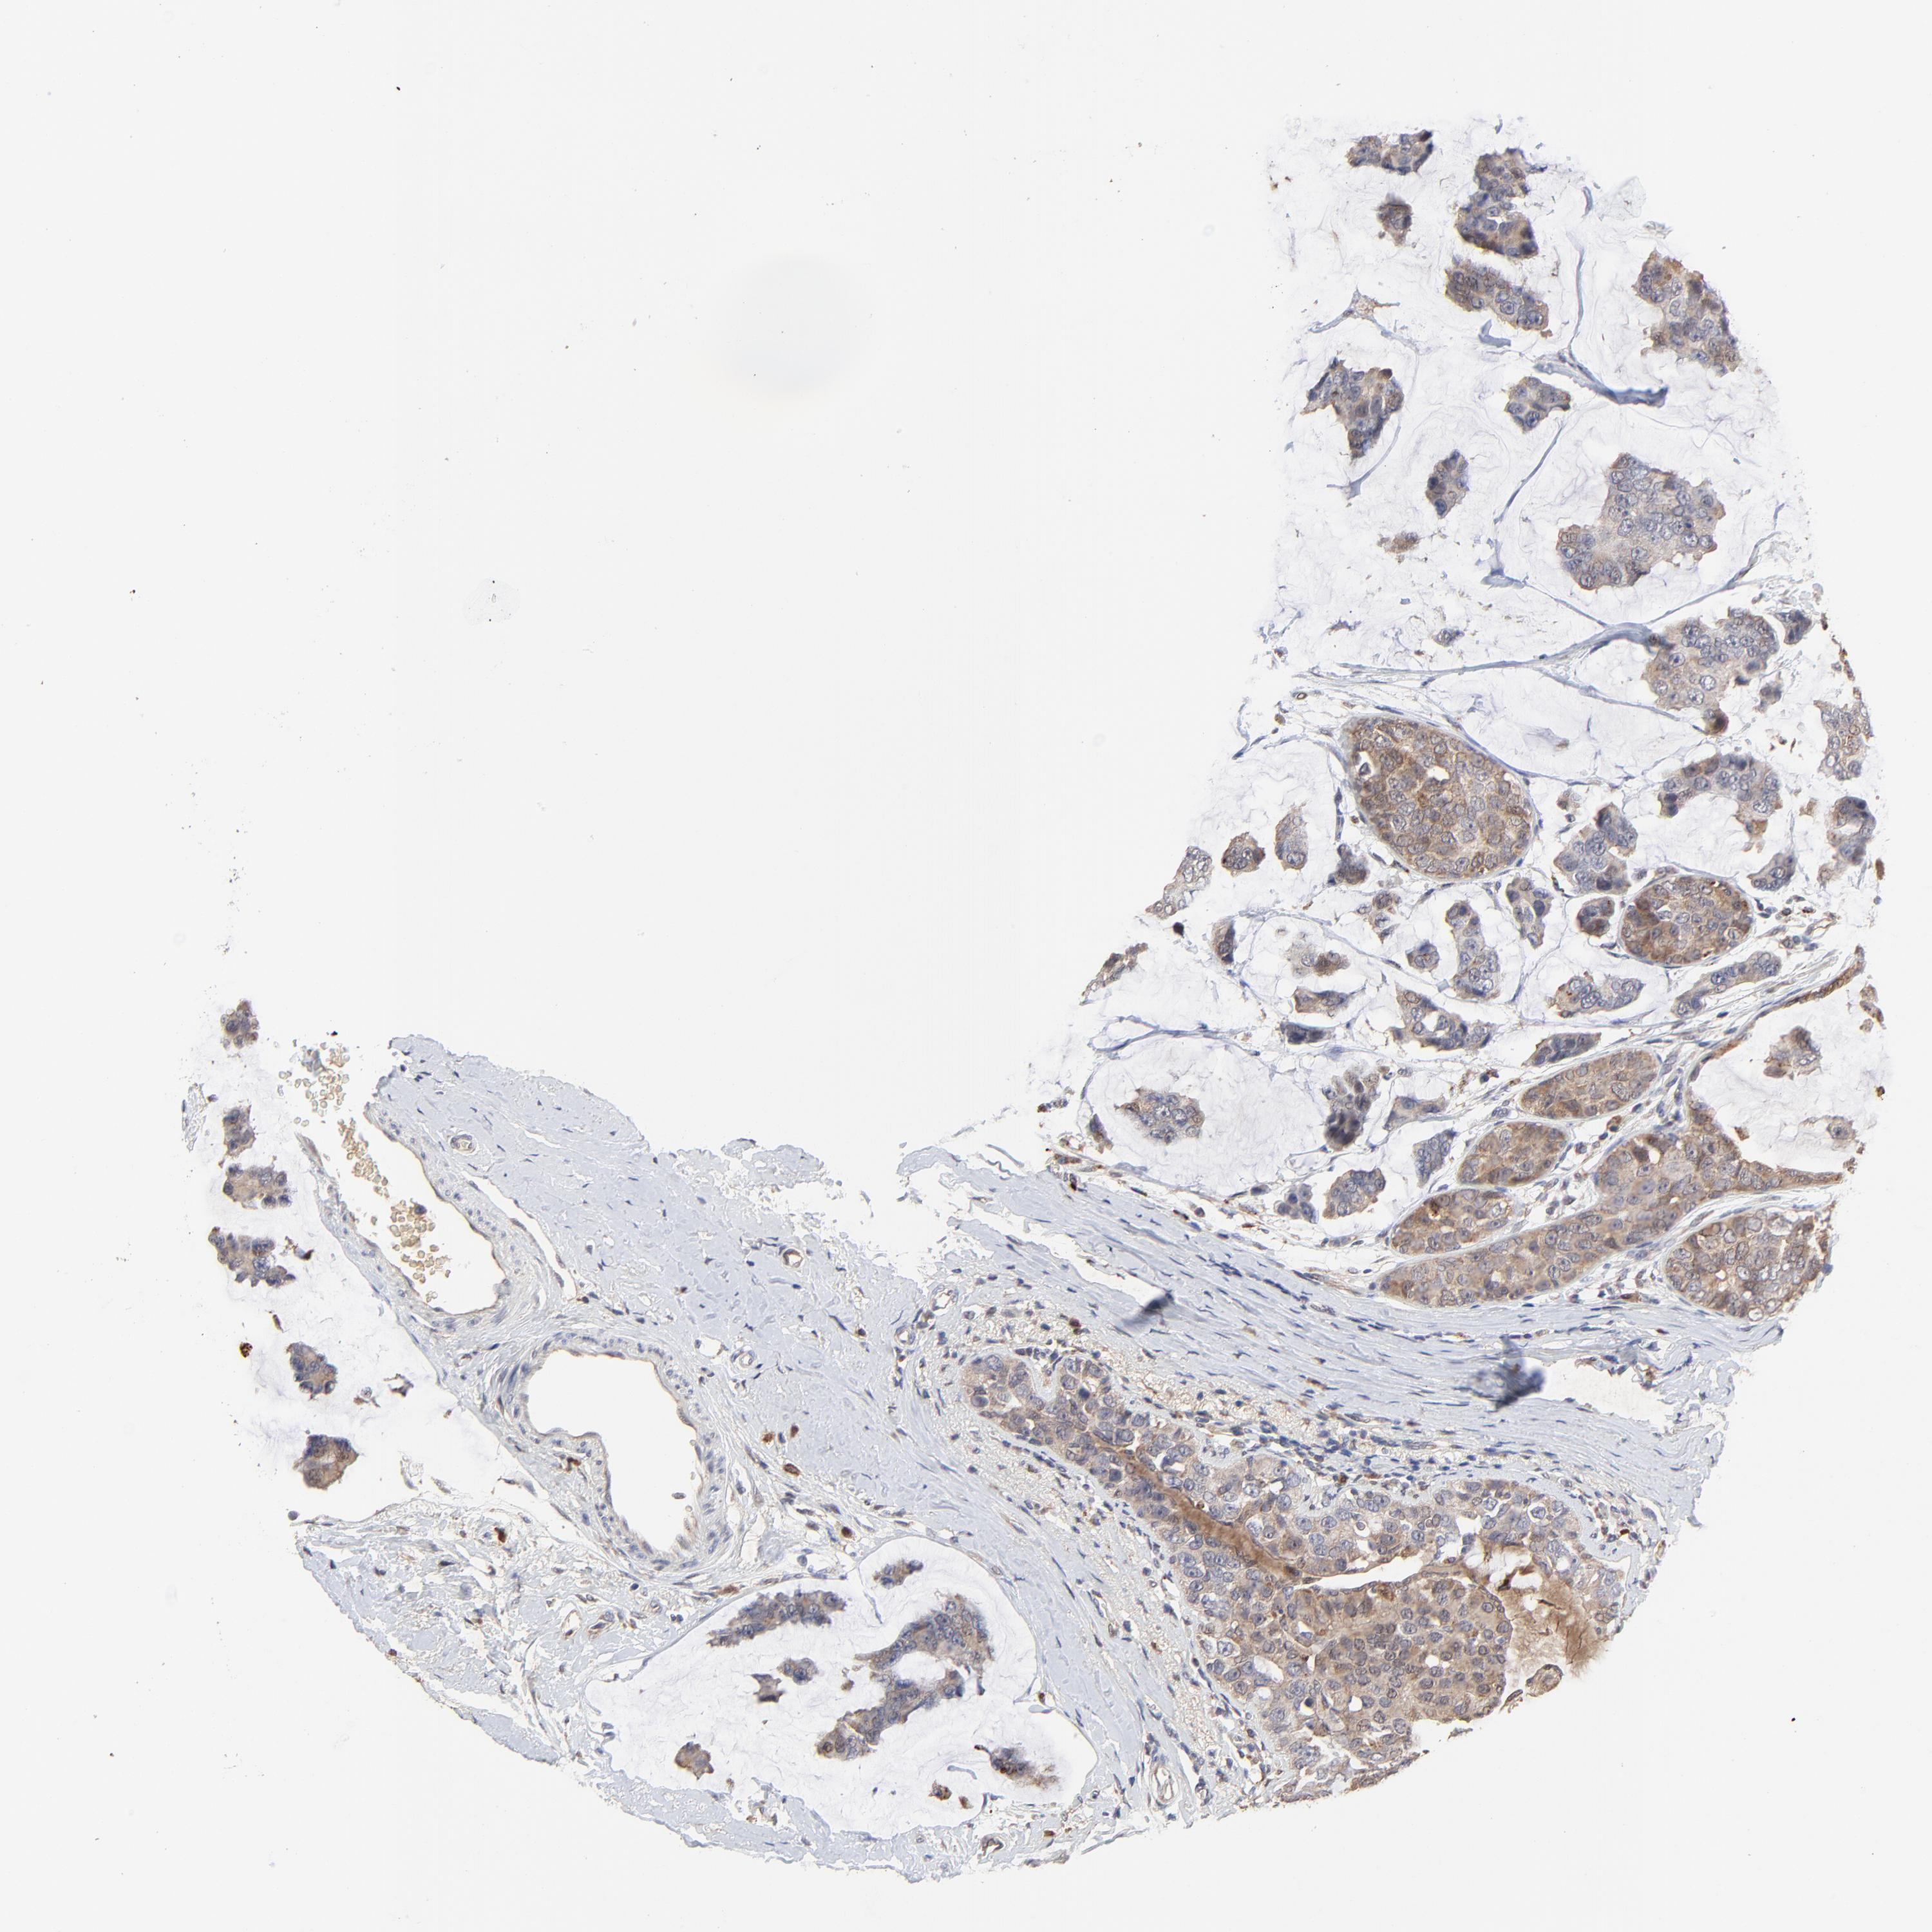

CANCER BREAST CANCER Show tissue menu

BRCA TCGA BRCA VALIDATION PROTEIN EXPRESSION

ANTIBODIES

AND

VALIDATION